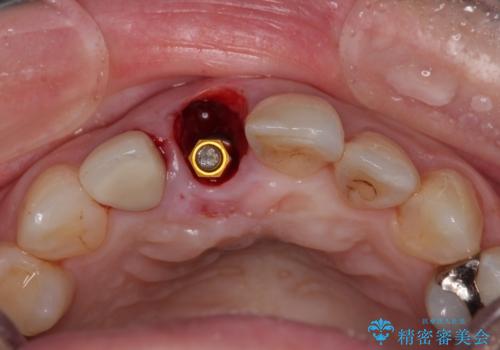

- 前歯のセラミッククランが外れてしまったとのことで来院された患者様です。

診察をしたところ、歯根に縦破折が認められ、抜歯が必要と判断されました。

抜歯、インプラント埋入、仮歯の装着が同時に可能な1DAYインプラントが適用可能と判断されたため、インプラントによる補綴治療を行うこととしました。

前歯のインプラント治療は、従来の抜歯から数ヶ月待機する手法では、骨造成や歯肉移植など付随の処置が多く必要となり、費用、期間、身体的負担のいずれもが多大となります。

抜歯時にインプラントを埋入することでそれらの負担を大きく軽減させることが可能です。